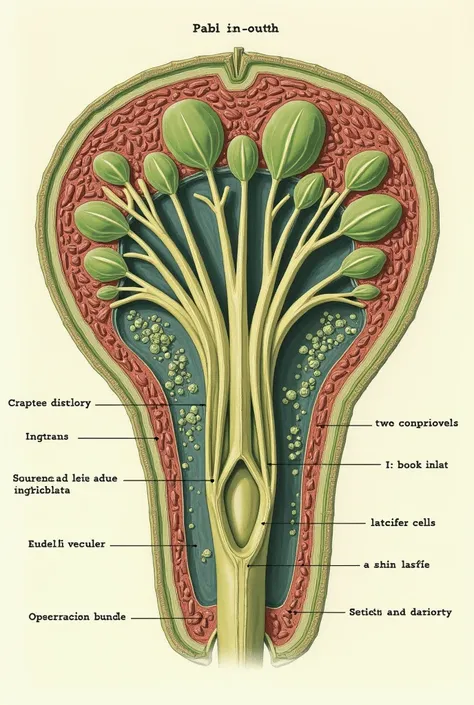

A diagram of the anatomy of the human body

Realice un dibujo de la piel. Coloque las siguientes referencias: Epidermis Fermis Hypodermis Keratinized squamous stratified epithelium Hair Sebaceous gland Sweat gland Pilo erector muscle Connective tissue Blood vessels Nerves Adipocytes

Epidermis Fermis Hypodermis Keratinized squamous stratified epithelium Hair Sebaceous gland Sweat gland Pilo erector muscle Connective tissue Blood vessels Nerves Adipocytes